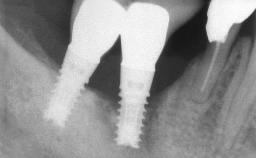

Oral implants are highly successful and offer long-term benefits, especially in the rehabilitation of edentulous patients or patients with oral defects following ablative tumor surgery (Albrektsson and coworkers 1986), and also after radiation therapy (Schiegnitz and coworkers 2014). With the number of implants placed globally going into the millions, implant dentists have observed some rare adverse events. Although carcinogenesis around implants is an exceedingly rare phenomenon, we recently reported about 15 patients treated for carcinomas adjacent to implants at our clinical department over a period of fifteen years (Moergel and coworkers 2014). The following case represents a patient of this cohort; it discusses possible risk factors and makes suggestions for a recall schedule. A 70-year-old woman was referred to our outpatient department for evaluation of a rapidly growing macroscopic alteration of the mucosa in the left mandible.

| # of Implants | 4 |